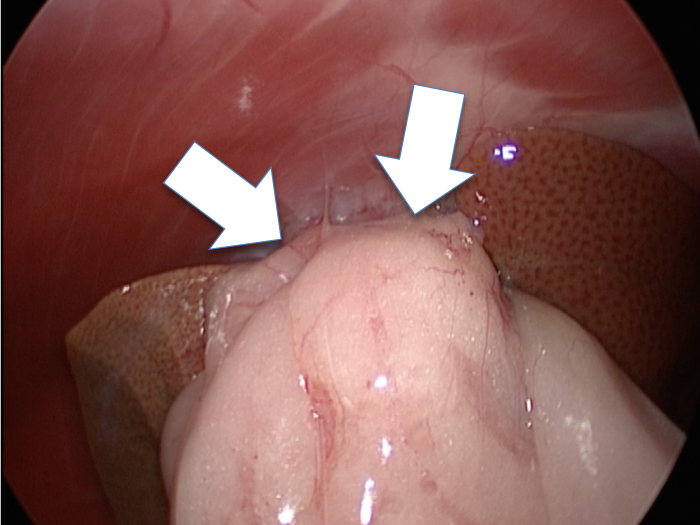

他院より紹介。胆嚢炎がひどく繰り返す嘔吐がありました。 腹膜と一部横隔膜に胆嚢ががっちりと癒着していました。 体重が2kgと体も小さかったのですが、飼い主さんの希望もあり、腹腔鏡下で手術を実施することになりました。

丁寧に丁寧に出血をコントロールしながら少しずつ手術をすすめていきます。

癒着(矢印)がひどく胆嚢を確認することができませんでした。

このように癒着しているときはギリギリで剥がすとひどく出血をおこすことがあるので無理にはがそうとしないで、脂肪の血管に注意しながら脂肪ごと剥がしていきます。